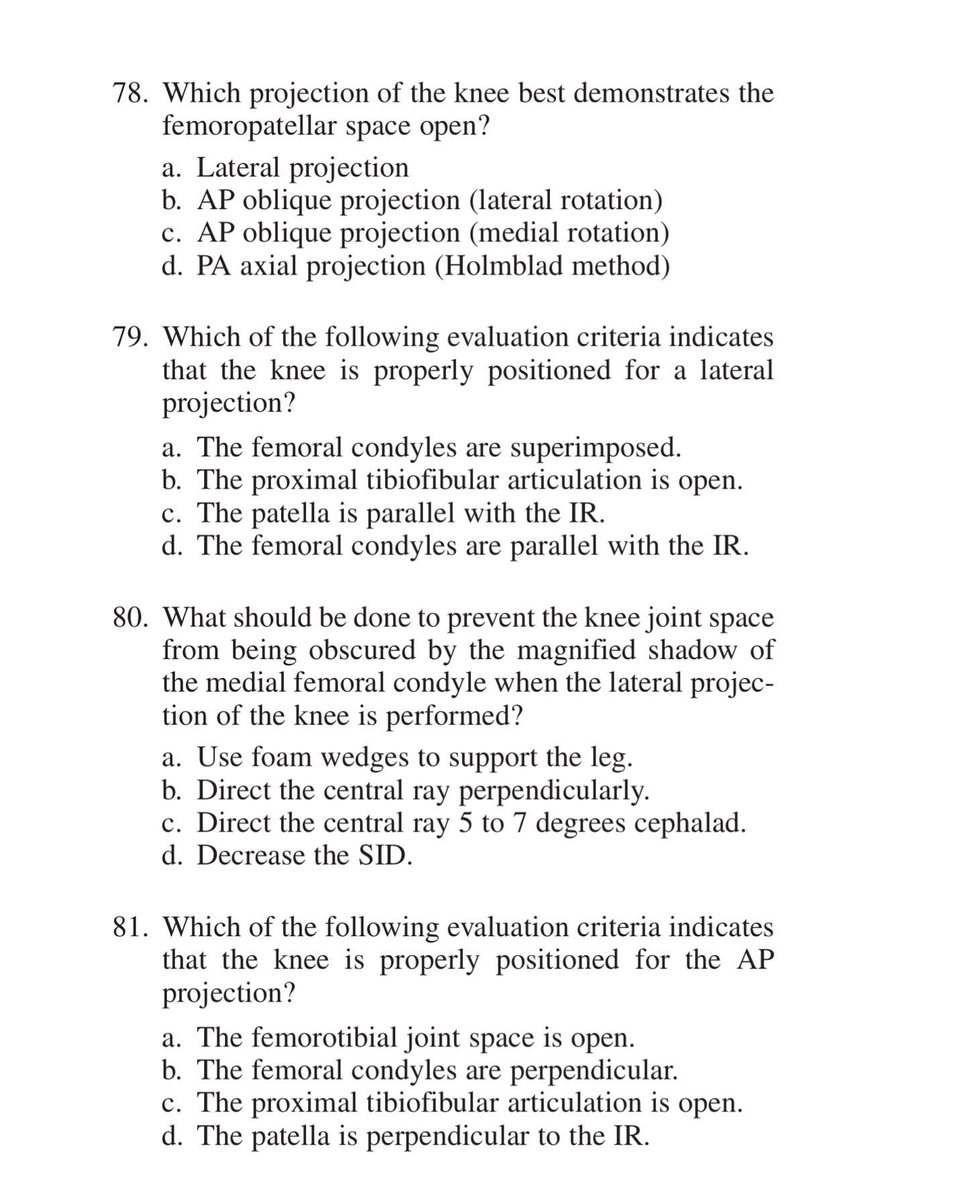

#radiology #radiography #xray #radiographer #radtech #srtle

من الاسئلة الاكثر أهمية في تصوير الركبة بالأشعة السينية فلنتشارك في الحل

SELF-TEST:

POSITIONING OF THE LOWER LIMB

Answer the following questions by selecting the best choice.

Reference (Merrill’s Atlas 12 edition)